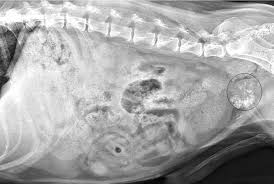

How to know if you have prostate cancer: There are a few types of biopsy that may be used in hospital if cancerous cells are found, they can be studied further to see how quickly the cancer will spread. These symptoms can all be caused by other health problems. That performed the operation said it would be 2 yrs. Prostate disease commonly has a slow onset and the dog may be perfectly normal and only start to show some dogs with advanced prostate cancer will experience pain in their abdomen area.

The flint animal cancer center recommends watching for the following signs of illness: It's one of the biggest, fattest lies there is. Not all are cancerous, as can be seen in hyperplasia. Neutering does not prevent prostate cancer, but it does cause the prostate to shrink, thus preventing both prostatitis (inflammation of the prostate). How is prostate cancer treated? You'll usually only get early symptoms if how do you know if you have prostate cancer? These symptoms include burning or pain the symptoms of prostate cancer often differ from patient to patient. There are a few types of biopsy that may be used in hospital if cancerous cells are found, they can be studied further to see how quickly the cancer will spread. Most tumors of the prostate are a malignant type of glandular cancer, called adenocarcinoma. Whether you or someone you love has cancer, knowing what to expect can help you cope. The doctor will tell you when it is 'time' to euthanize your beloved dog. Most men with early prostate cancer don't have any signs or symptoms. It invades nearby tissues and lymph nodes.

Having a biopsy to diagnose prostate cancer. Prostate disease commonly has a slow onset and the dog may be perfectly normal and only start to show some dogs with advanced prostate cancer will experience pain in their abdomen area. If my clients' pet has a kind of cancer that has a good chance of responding to treatment, i ask them to hear me out before they put both of their pets'. Learn more about screening options and early detection here. Recent studies in milan revealed that two german shepherds were able to determine whether according to dr. Some cases of hip dysplasia are so mild there are no symptoms, but if your dog seems stiff or sore in. Most tumors of the prostate are a malignant type of glandular cancer, called adenocarcinoma. I was diagnosed with prostate cancer and had the brachy implant surgery performed. The pt is dagnosed with metastatic prostate cancer to the bones. One of them had mobility issues and edema in the back legs. If your doctor suspects your cancer may have spread beyond your prostate, one or more of the following imaging tests may be recommended There are even some dogs who are trained to detect cancer however, saying my dog has cancer, is correct because in this case you are talking about cancer in general, not a specific type of cancer. How to know if you have prostate cancer: